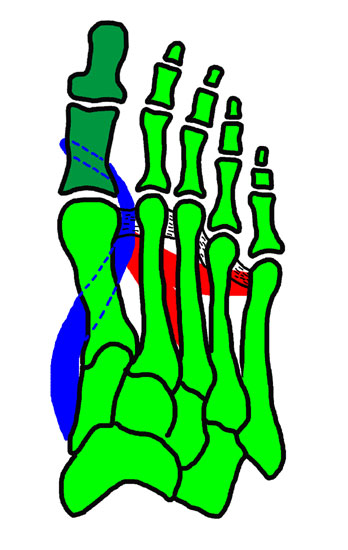

Zusammenhänge der adduzierenden und abduzierenden Muskelkräfte <a class=15, (Janis 1975)" title="Zusammenhänge der adduzierenden und abduzierenden Muskelkräfte 15, (Janis 1975)" width="345" height="550">

Abbildung 6: Zusammenhänge der adduzierenden und abduzierenden Muskelkräfte 15, (Janis 1975)